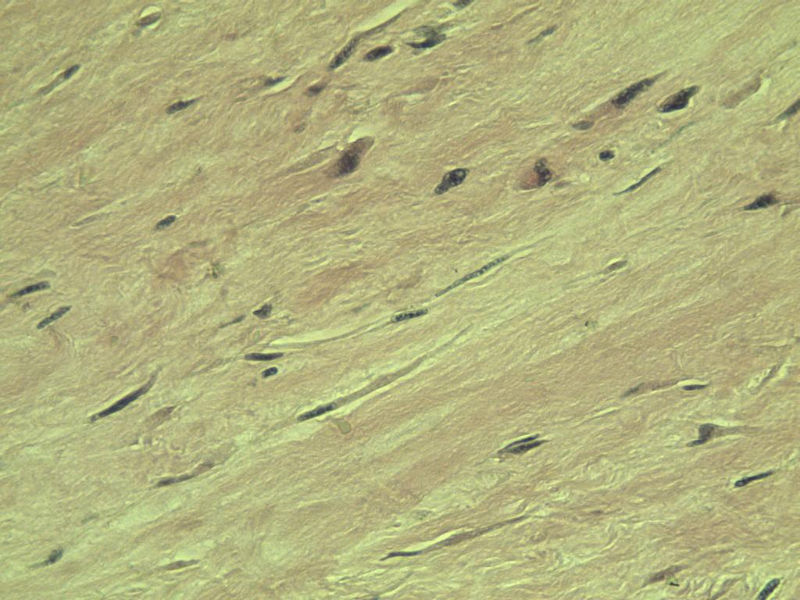

男,51岁, 4月前患者无意中发现右腘窝一包块,约核仁大小无疼痛, 4月来包块进行性生长

灰褐类圆形包块一个,直径 5 cm,切面灰白,实性,编织状。 请各位老师看看 是什么? 谢谢!